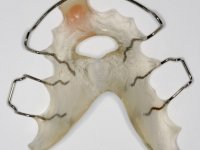

Tendo em conta a relação de Classe II molar e canina, o plano de tratamento contemplou a seguinte abordagem multidisciplinar:

1) Extracção do 2º pre-molar superior direito,

2) Tratamento ortodôntico com o objectivo de criar espaço entre as raízes e as coroas dos dentes 11 e 22,